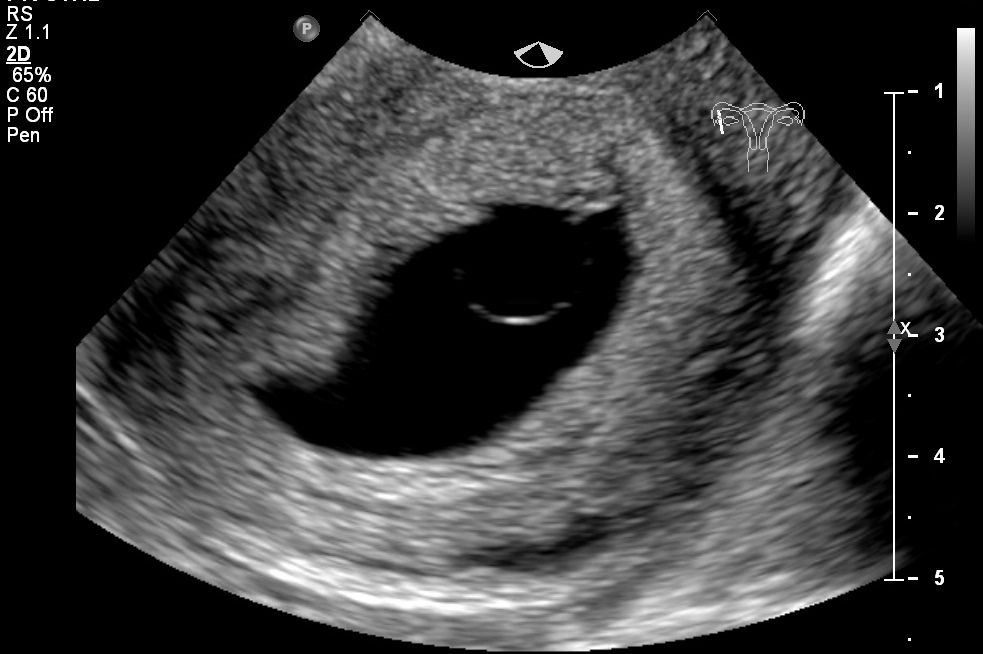

Late blighted ovum missed miscarriage how fast your body deals with the loss.

At what stage do blighted ovums usually miscarry. My first mmc baby stopped growing at 7 5 weeks we found out at 8 5 week appointment it was 4 weeks later we officially miscarried. It means than blighted ovum may appear up to 2 months before miscarriage. They most commonly expel naturally between 7 and 12 weeks.

In the same time blighted ovum is responsible for 50 of miscarriages which occurred in the first trimester. This is usually called a missed miscarriage. A woman s body recognizes abnormal chromosomes in a fetus and naturally does not try to continue the pregnancy because the fetus will not develop into a healthy baby. We found out at 7 weeks that this pregnancy is most likely a blighted ovum.

A blighted ovum causes about one out of two miscarriages in the first trimester of pregnancy. You can take a pill called misoprostol which causes your uterus to clear its contents or have a brief surgical procedure called a dilation and curettage d c. I go for another ultrasound at 8w6d to confirm and then my doctor thinks once i stop my progesterone my body will just do it s thing naturally. If your blighted ovum does not miscarry naturally after a few weeks your doctor may recommend medication or surgery.

Some occur as spontaneous losses very early. A miscarriage is when a pregnancy ends on its own within the first 20 weeks. Blighted ovums miscarry at different stages. I am so scared to miscarry at home even though there isn t an actual fetus.